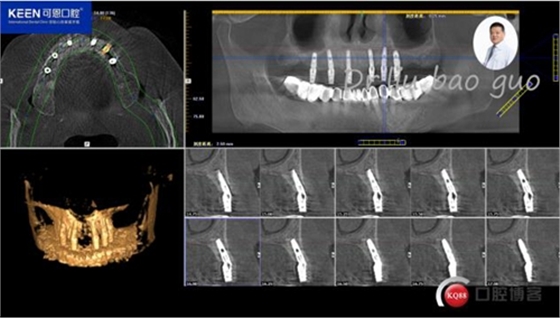

手術(shù)前種植軟件設(shè)計(jì)方案